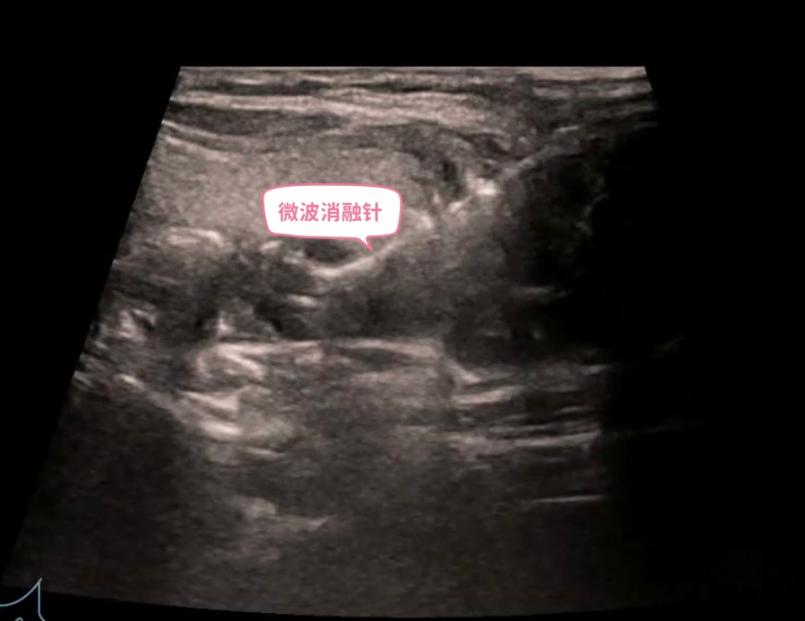

甲状腺和甲状旁腺微波消融治疗是国内近年来逐步开展并推广的一种新型微创治疗技术。在超声的精准引导下,通过一根消融针产生局部高温,以杀死靶细胞,达到灭活病灶或肿瘤的效果。

针对病灶紧贴喉返神经的难题,孙德胜带领团队首先用上了创新的 “水隔离”技术技术通过细针在目标病灶与喉返神经等关键组织之间,注入生理盐水,人为地创造出一个安全的“隔离带”,为手术上了“第一道保险”。

随后,在超声的实时、高清引导下,微波消融电极化身为精准的“导弹”,沿着安全路径直达已成为“水中孤岛”的增生腺体。启动消融,热能精准释放。整个核心消融过程仅历时42秒,从穿刺到完成,总手术时间约20分钟。

手术后即刻进行的超声造影证实,异常增生的甲状旁腺被成功、完全灭活。整台手术实现 “零出血”术后监测证实,患者临床症状便得到显著改善,血清甲状旁腺激素(PTH)水平有效下降,无声音嘶哑,喉返神经功能完好无损。